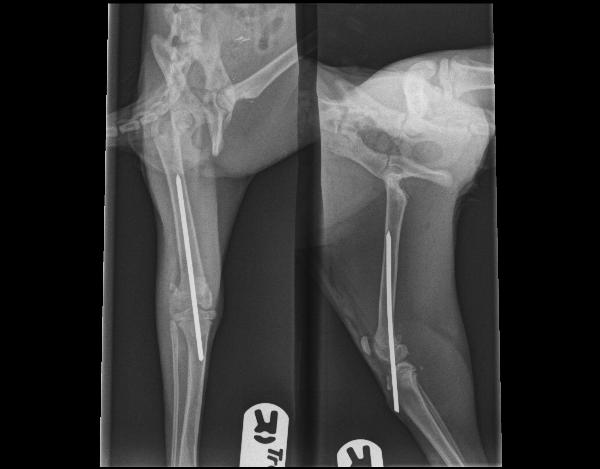

Ok, Sevgi is thuis. Ondanks het kalmeringsmiddel blijft ze niet rustig in de bench (ze klimt). Ik ga de bench maar eens in hoogte beperken met stevig karton denk ik.

SPOILER: x-ray